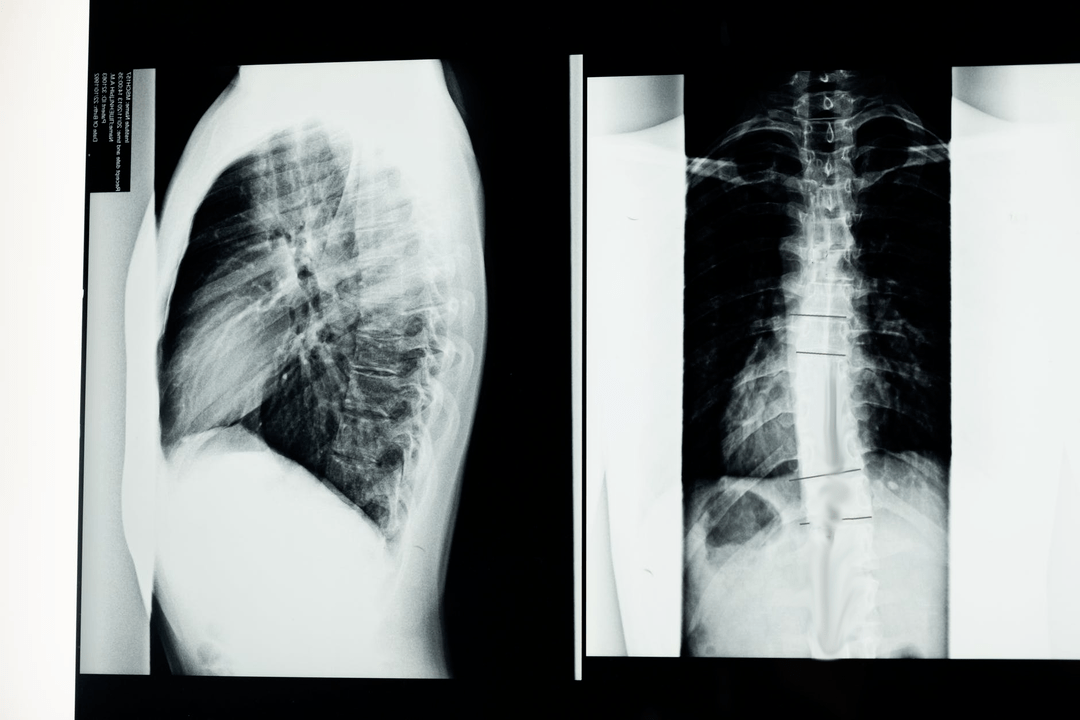

As with any diagnosis in medicine, the diagnosis of osteochondrosis is made on the basis of the patient's complaints, medical history, clinical examination and auxiliary research methods. The cervical spine x-ray is performed in frontal and lateral projections, if necessary in specific positions (open mouth). At the same time, specialists are interested in the height of the intervertebral discs and the presence of osteophytes.

Among modern research methods, NMR and CT studies are used, which allows the most accurate verification of the diagnosis. In addition to the additional research methods listed, you may need to consult related specialists (cardiologist, ophthalmologist, neurosurgeon), and examination by a neurologist is simply vital. A neurologist is engaged in the treatment of osteochondrosis. Therefore, after examining the patient, he will, at his discretion, prescribe the minimum necessary examination.